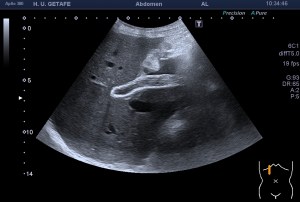

Compara estos dos quistes de Baker, si los miras bien son prácticamente iguales. Hay una diferencia muy importante entre tanta igualdad…uno es normal, el otro es patológico. Las tres últimas imágenes, 5 a 7, corresponde a un quiste de Baker infantil, por tanto se considera un hallazgo que puede ser normal para estas edades, esta figura en a edad adulta es siempre patológica y en relación con artrosis y cambios degenerativos de la articulación.

Por tanto, en la infancia se desconoce la forma clara el mecanismo por el que se produce. Podría estar relacionado con el desarrollo de la rodilla, pero a diferencia del adulto, su presencia no refleja ningún tipo de alteración intraarticular de la rodilla.

Imágenes idénticas de figuras patológicas que en el caso de la edad infantil no revisten más importancia y solo necesitan control. La exeresis de estos quistes no elimina la posibilidad de que se reproduzcan.